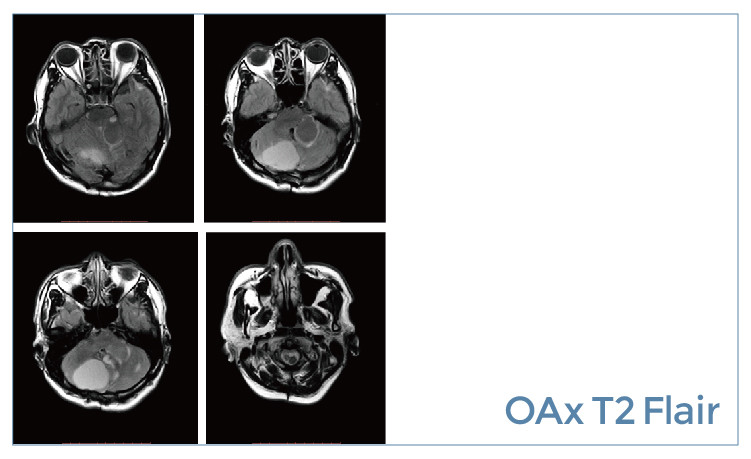

【朗润影像档案】20190614磁共振影像病例结果讨论